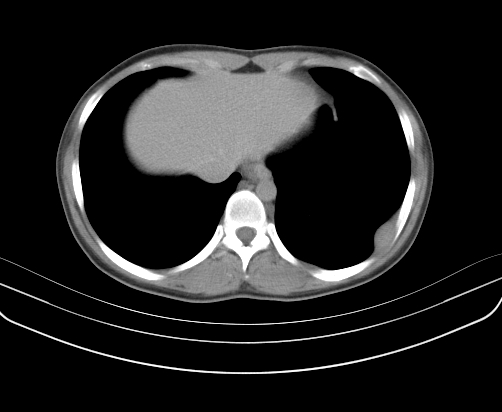

胸部